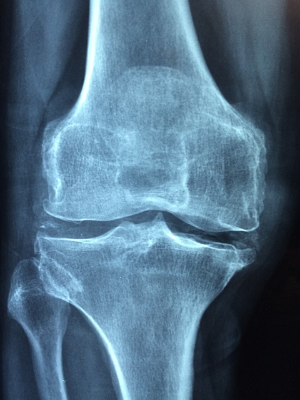

콘드로이친은 주로 관절을 둘러싼 연골을 구성하는 물질로, 젊었을때는 체내에서 잘 생성되지만 연령이 증가하면서 체내에서 합성하는 능력이 저하되어, 중년이 되면 몸에서 필요한 양의 5% 밖에 생성되지 않는다고 합니다. 콘드로이친이 결핍되면 연골의 탄력이 떨어지고 닳을 수 있기 때문에 하루 1200mg의 섭취가 권장됩니다.콘드로이친 1200mg 효능

연구에 따르면 콘드로이친은 관절 건강에 상당한 효능을 보일 수 있다고 합니다. 콘드로이친 1200mg의 효능으로는 관절 통증을 줄이고, 관절 기능을 향상시키며, 골관절염의 진행을 늦추는 데 효과가 있다고 합니다.

콘드로이친 1200mg은 연골에 물을 끌어들여 충격 흡수 능력을 높이고, 이를 통해 관절 건강을 증진시킨다고 알려져 있습니다.

게다가, 콘드로이친은 관절염의 진행을 늦추는 것으로 발표되었습니다. 관절염의 특징으로, 연골의 퇴화는 시간이 지남에 따라 관절 손상과 악화로 이어지게 되는데 연구에 따르면 콘드로이친은 연골을 보호하고 보존하는 데 도움을 줄 수 있으며, 잠재적으로 퇴행 과정을 늦추고 관절 건강을 유지할 수 있습니다.